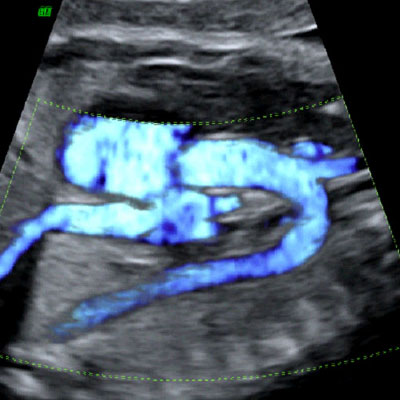

High definition flow of the fetal aortic arch

Legend:High definition flow of the fetal aortic arch